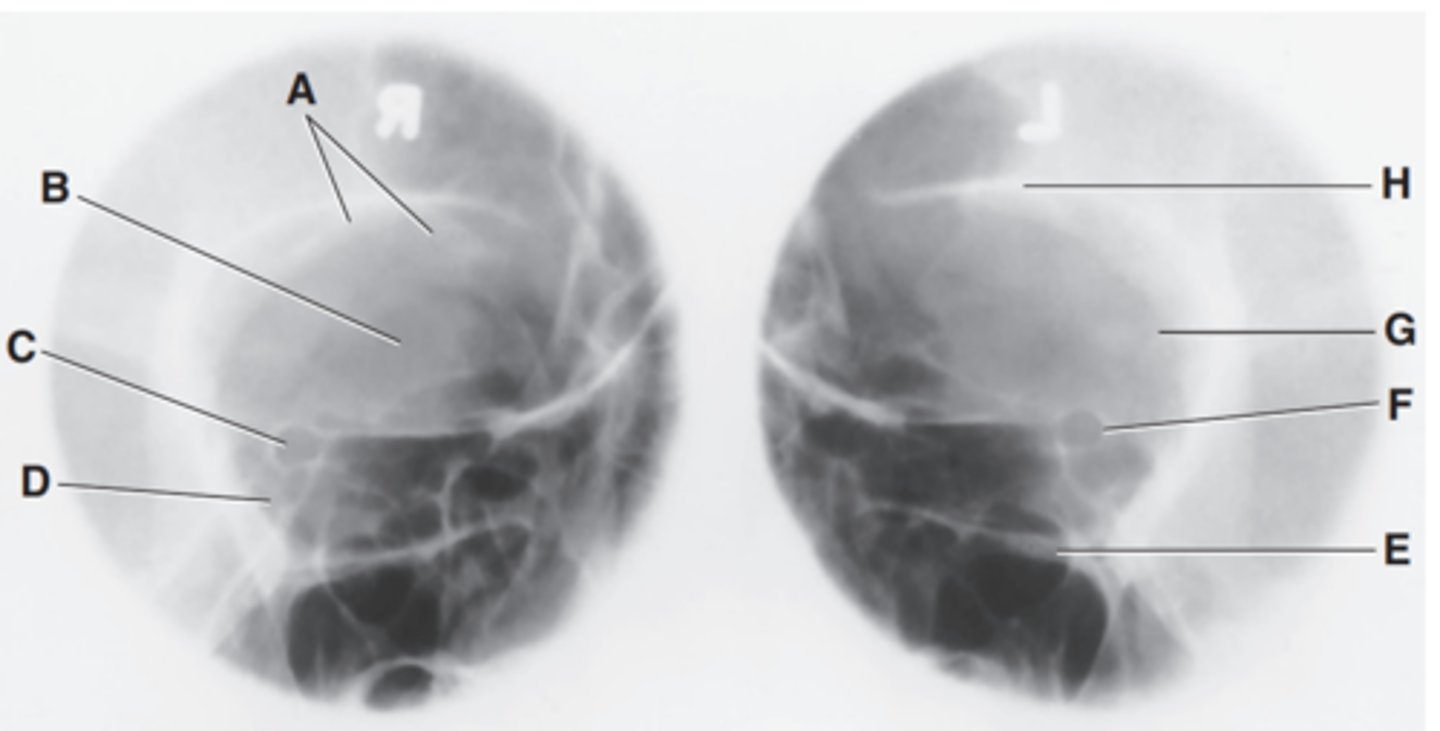

Orbital plate of frontal bone

Label A

Sphenoid bone

Label B

Optic foramen and canal

Label C

Superior orbital fissure

Label D

Infraorbital margin (IOM)

Label E

Sphenoid strut

Label F

Lateral orbital margin

Label G

Supraorbital margin

Label H